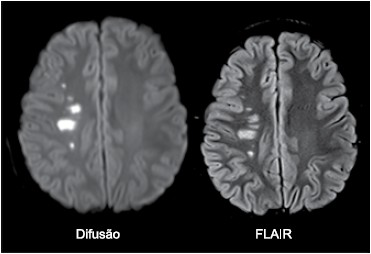

Paciente do sexo feminino, 10 anos, apresenta quadro de hemiparesia completa à esquerda de início súbito. Realizou a ressonância magnética de crânio mostrada a seguir.

O diagnóstico é

Paciente do sexo feminino, 10 anos, apresenta quadro de hemiparesia completa à esquerda de início súbito. Realizou a ressonância magnética de crânio mostrada a seguir.

O diagnóstico é